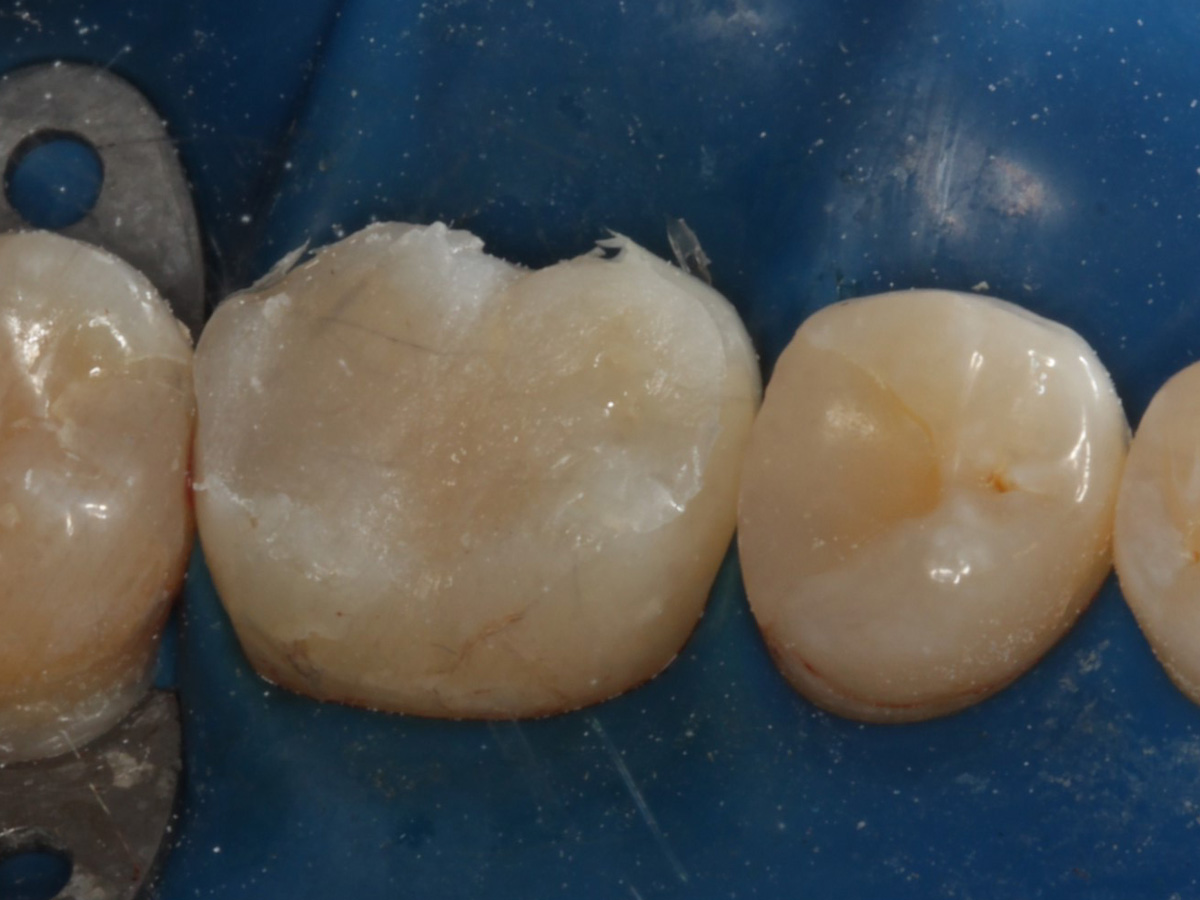

Kavitäten gefüllt (Injektion Moulding: Flowkomposit, erwärmtes Seitenzahnkomposit aus Karpule)

Abbildung 20

Abbildung 21

Zahnseidenkontrolle: kein Überschuss, satte Kontaktpunkte